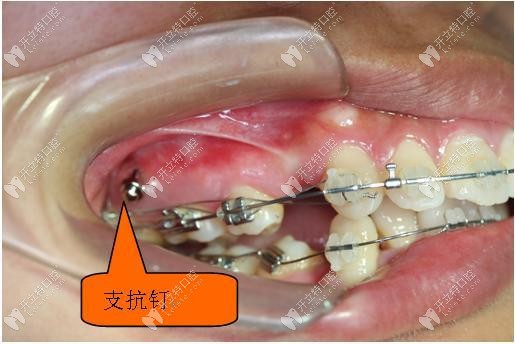

口腔種植體支抗是將純鈦制作的特殊的微小鈦釘植入到患者的上頜后牙區(qū)、下頜后牙區(qū)、硬腭部,牙齒槽間隔等等的部位,利用這種植入的微小鈦釘作正畸治療的支抗,牽引排列不齊的牙齒作移動(dòng),從而達(dá)到矯治牙列不齊的目的。

支抗釘在矯正過(guò)程中可適用的位置